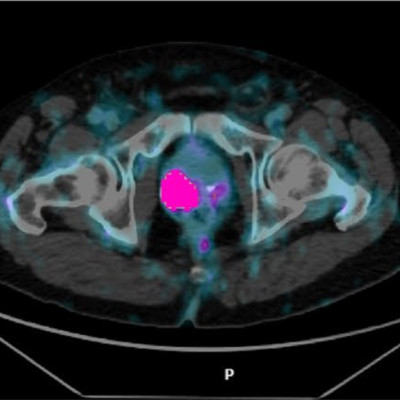

Analytical performance validation of aPROMISE platform for prostate tumor burden